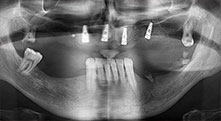

Bratu: Utilizamos los insertos de forma rutinaria para la extracción de injertos óseos y la ranuración de las crestas alveolares. También utilizamos las Piezomed B6/B7 para practicar osteotomías en dientes retenidos y no retiramos implantes que pueden conservarse. Todas estas son indicaciones que requieren cortes profundos y limpios.

Bratu: Nos gusta utilizar la técnica de sándwich para realizar aumentos en la cara lateral del maxilar inferior. En este procedimiento, se utiliza la sierra piezoquirúrgica para preparar una tapa ósea, mientras que el fragmento crestal se fija con microtornillos. Entre medias, colocamos una combinación de hueso autólogo y material óseo adicional xenógeno. Y con ello obtenemos un rendimiento muy fiable. Asimismo, en los ranurados de la cresta alveolar del maxilar inferior, nunca se puede prescindir de cortes verticales suficientemente dimensionados, pues, de lo contrario, los huesos pueden fracturarse fácilmente.